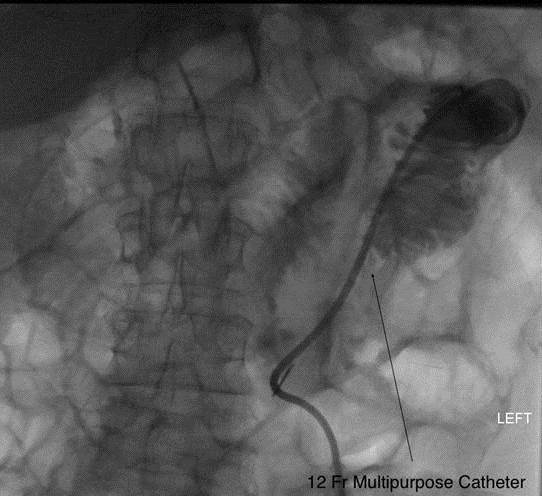

#caregivers,#irad places direct jejunostomy#FeedingTubes for chronic#aspiration patientspic.twitter.com/j1fjmgqK5z